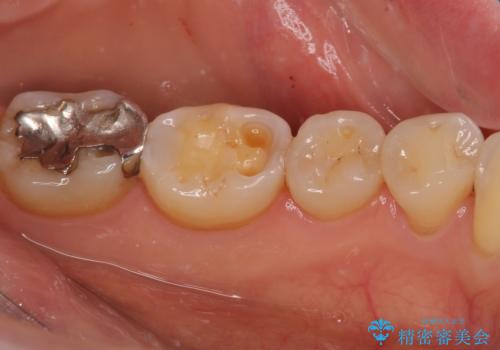

奥歯の銀歯をゴールドでしっかりと治療

ゴールドは「白い歯」ではありませんが、銀歯の金属色とは異なり、非常にきれいな色合いが特徴です。

もちろん、適合が極めて良いという圧倒的メリットもゴールドクラウンやゴールドインレーの特徴です。